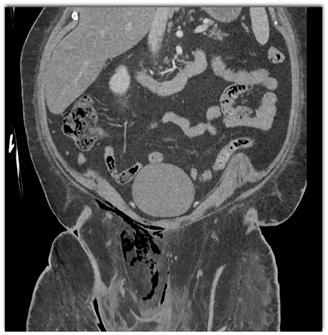

The best diagnosis in this febrile patient is?

rectal perforation

foreign body perforation

necrotizing fasciitis

pelvis abscess